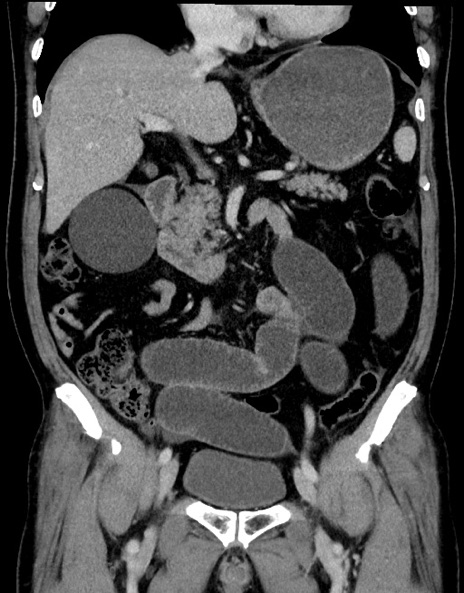

横断像

【症例】70歳代男性

【主訴】腹痛

【現病歴】今朝から腹痛あり。全体的に痛い。特に左上の方。排ガスが今日はない。冷や汗が出る。

【既往歴】直腸癌術後

【身体所見】左側腹部〜上腹部に圧痛あり。腹膜刺激症状明らかなではない。軽度反跳痛。左下腹部に術後瘢痕あり。

【データ】WBC 7700、CRP 0.02